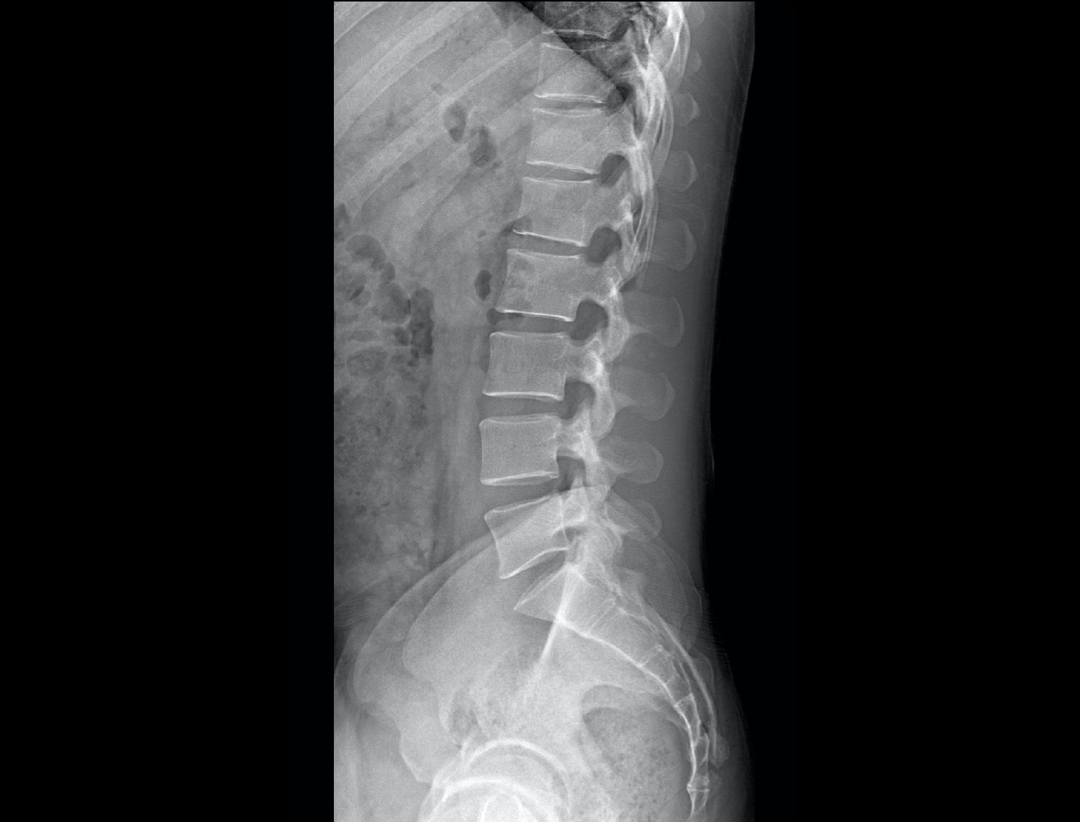

支持自动立位及卧位无尺全景拼接,为骨科、整形外科提供高质量全景影像。

集成脊柱Cobb角及股骨颈干角测量功能,精准指导外科手术及术后评估。

全脊柱正位、侧位

腰椎正位、侧位